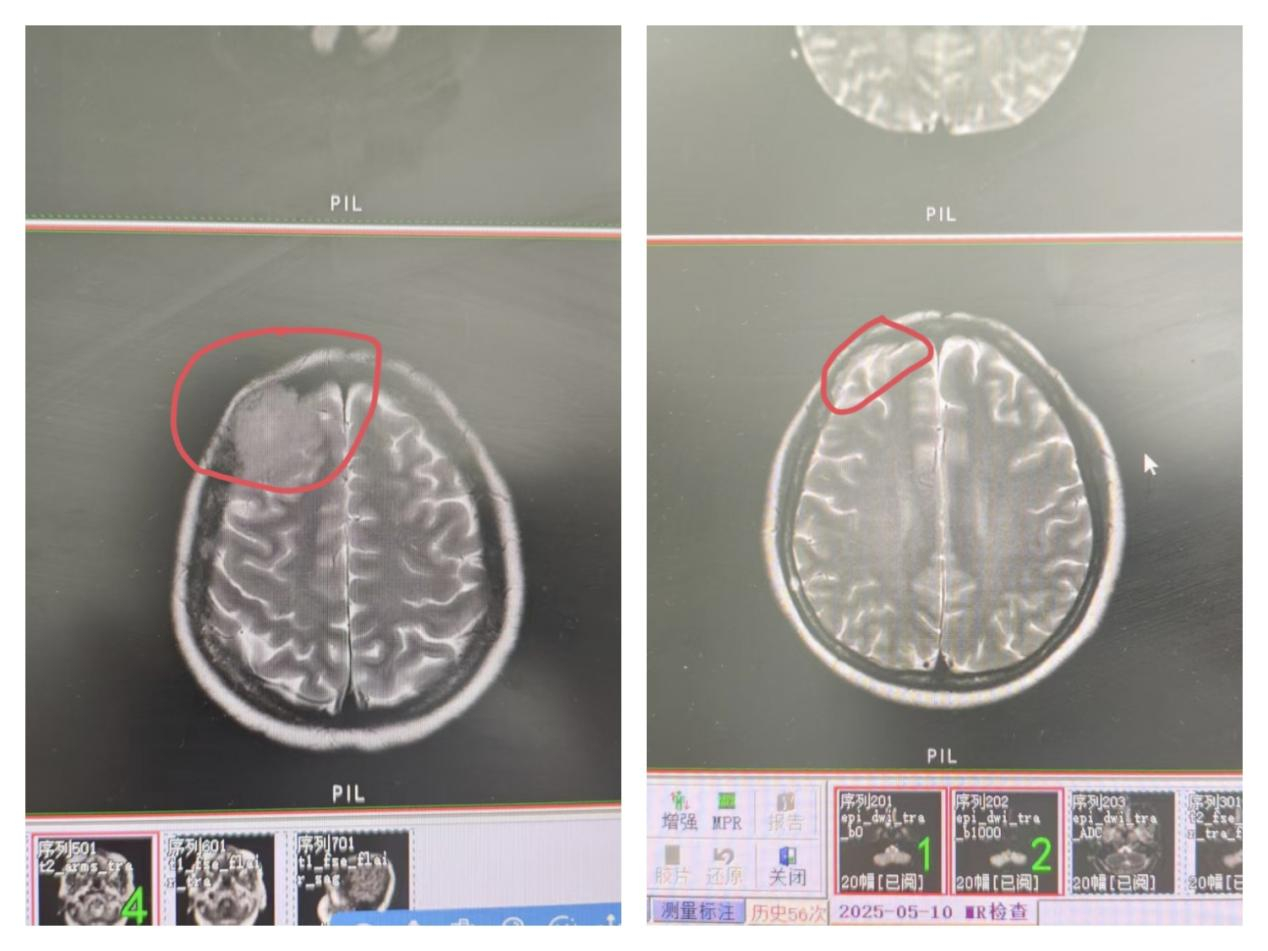

图片6.邹女士头颅磁共振治疗前后对比

2021年春,邹女士确诊多发性骨髓瘤的消息如晴天霹雳,打破了一家人平静的生活。三年间,化学治疗、骨髓穿刺、骨髓移植……她咬着牙挺过一次次治疗,病情却如潮水般反复。2024年秋,命运竟再次发难,邹女士颅脑磁共振显示:右侧额部颅骨出现多发性骨髓瘤髓外浸润,肿瘤细胞如藤蔓般侵入颅骨。骨髓活检:肿瘤细胞占比80%,完善PET\CT提示:多发性骨髓瘤并髓外浸润。

秋去春来,就这样坚持近半年,皇天不负有心人,在2025年春,邹女士头颅包块肉眼可见的缩小,磁共振提示颅骨髓外包块较前大幅度收缩,骨髓活检多次提示肿瘤细胞得到消除,体力较前明显恢复,现坚持每日快走打卡也不觉得特别疲惫,日均步数在一万以上。科室和邹女士都相信继续坚持治疗一定会越来越好。曾英坚主任医师团队也是因此收到了来自邹女士发自真心感谢的锦旗,这面锦旗是对目前治疗效果的充分肯定,也是对后续治疗的满怀信心。